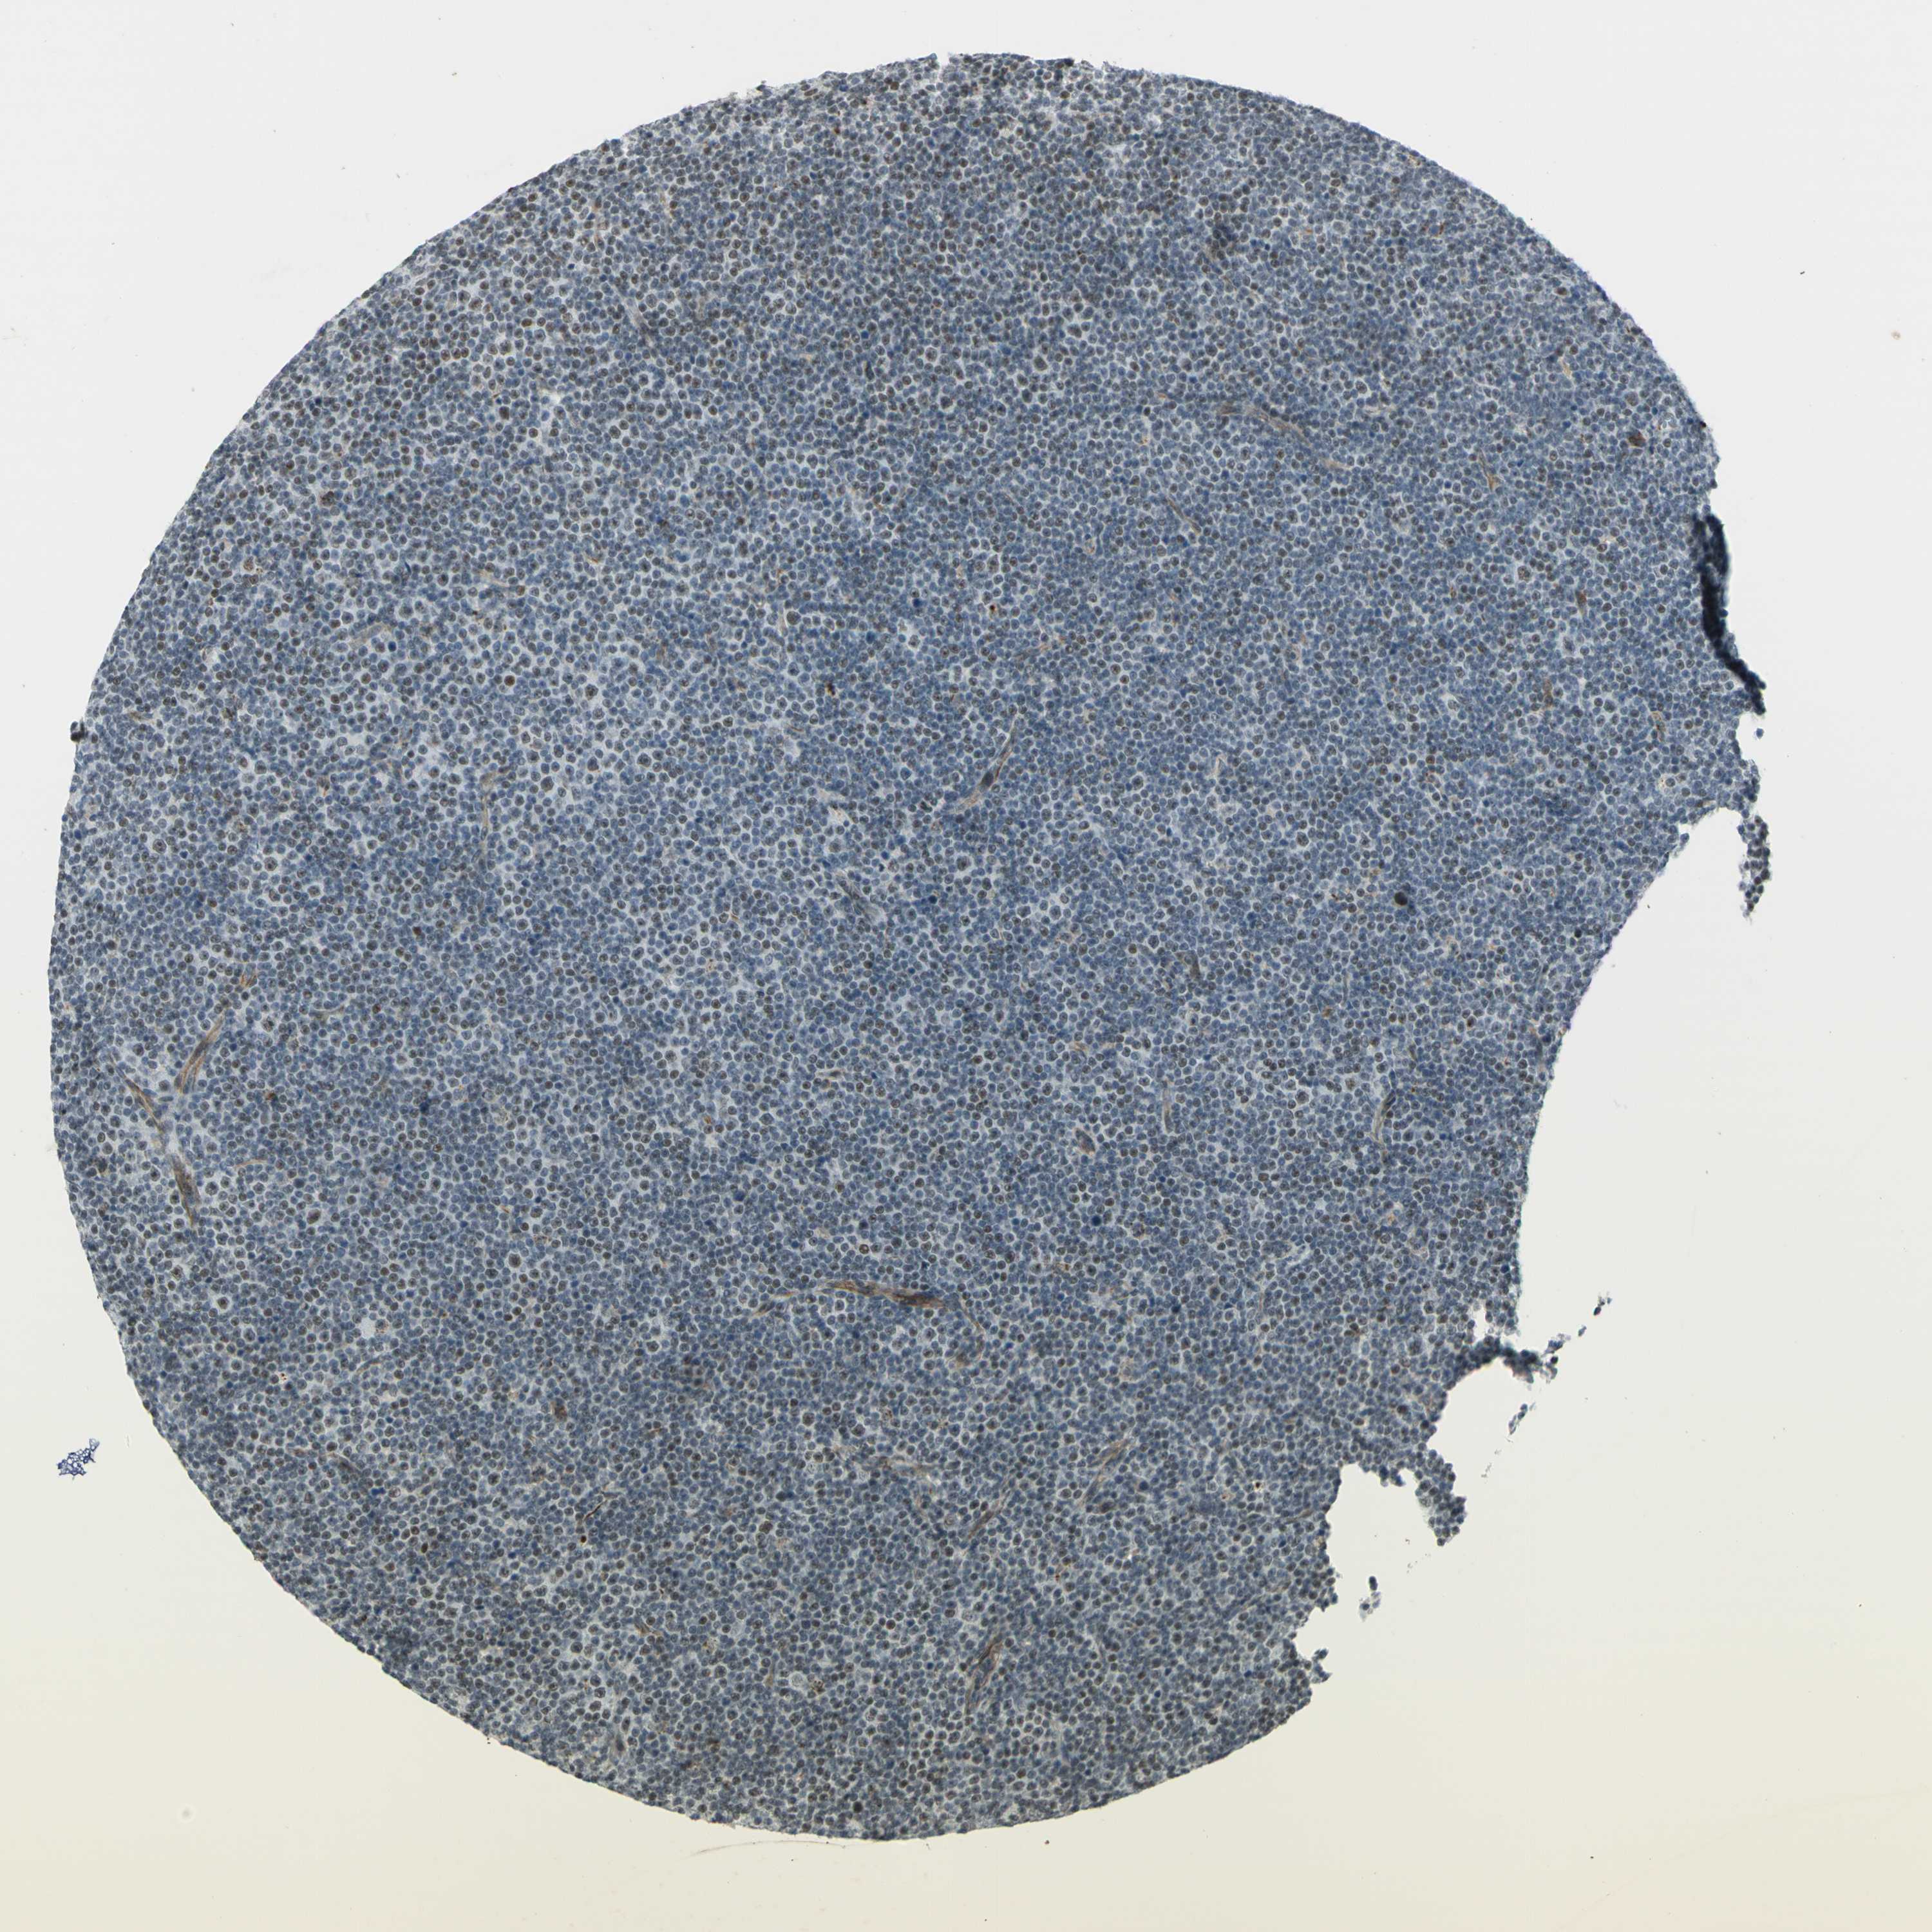

LYMPHOMA - Protein expressioni

A mouse-over function shows sample information and annotation data. Click on an image to view it in a full screen mode. Samples can be filtered based on level of antibody staining by selecting one or several of the following categories: high, medium, low and not detected. The assay and annotation is described here.

Antibody staining in the annotated cell types in the current human tissue is reported as not detected, low, medium, or high, based on conventional immunohistochemistry profiling in selected tissues. This score is based on the combination of the staining intensity and fraction of stained cells.

Each image is clickable and will lead to virtual microscopy that enables deeper exploration of all samples and also displays staining intensity scores, fraction scores and subcellular localization as well as patient and tissue information for each sample.

Antibody HPA063131

Antibody CAB011662

Malignant lymphoma, non-Hodgkin's type, Low grade

Malignant lymphoma, non-Hodgkin's type, High grade

Hodgkin's disease, NOS

Hodgkin's lymphoma, nodular sclerosis